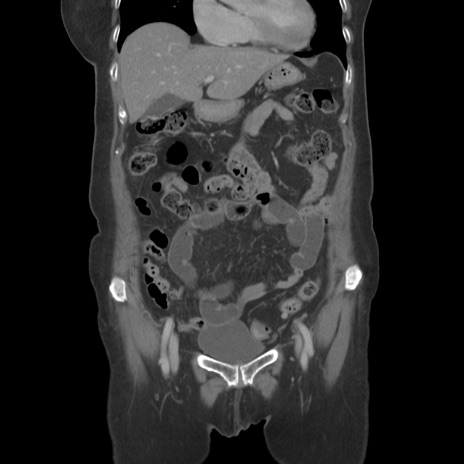

症例19(冠状断像)

【症例】80歳代女性

【主訴】下腹部痛

【現病歴】約8時間前より下腹部痛の出現あり、救急外来受診。

【既往歴】両側付属器切除

【身体所見】意識清明、下腹部正中に手術痕あり、その部位に一致して圧痛と反跳痛あり。腸蠕動音は亢進。

【データ】WBC 9300、CRP 0.15